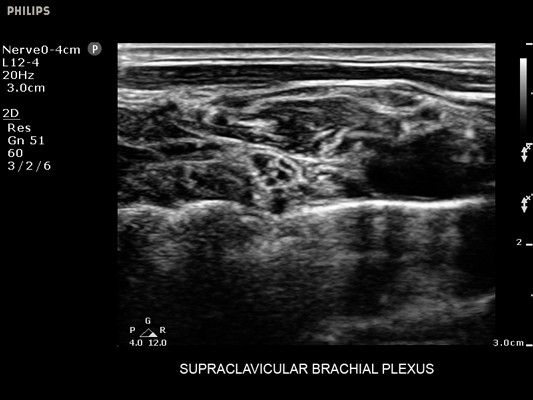

• Метки центральной линии на датчиках L12-4 и C6-2 для упрощения внеплоскостной навигации

• Диагностика нервов

• Линейный УЗИ датчик Philips L12-4